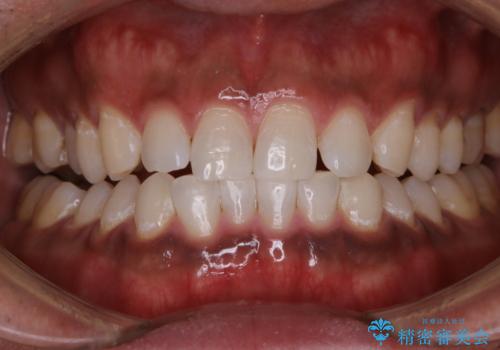

- 20代男性

- 1日

- 1回

- 数年ぶりにホワイトニングを希望とのことで、できる限り白くしたいとのことでした。

オフィスホワイトニングのエクセレントコースを行いました。

- ¥29700費用は治療当時の料金となります